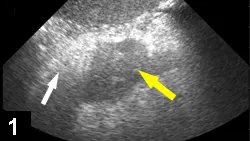

Figure 2. Radiograph confirming appropriate postoperative placement of a nasogastric tube in a dog.

• Nasogastric tubes allow aspiration of gastric contents, which may decrease nausea and vomiting and help prevent aspiration pneumonia (See Figures 2 and Figure 3).